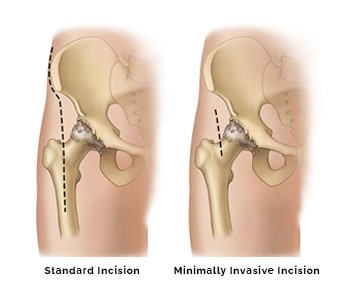

MBBS, M.Ch - Orthopaedics, MS - Orthopaedics Orthopedic surgeon,Joint Replacement Surgeon,Spine Surgeon (Ortho)

Director - Joint Replacement , Arthroscopy And Spine